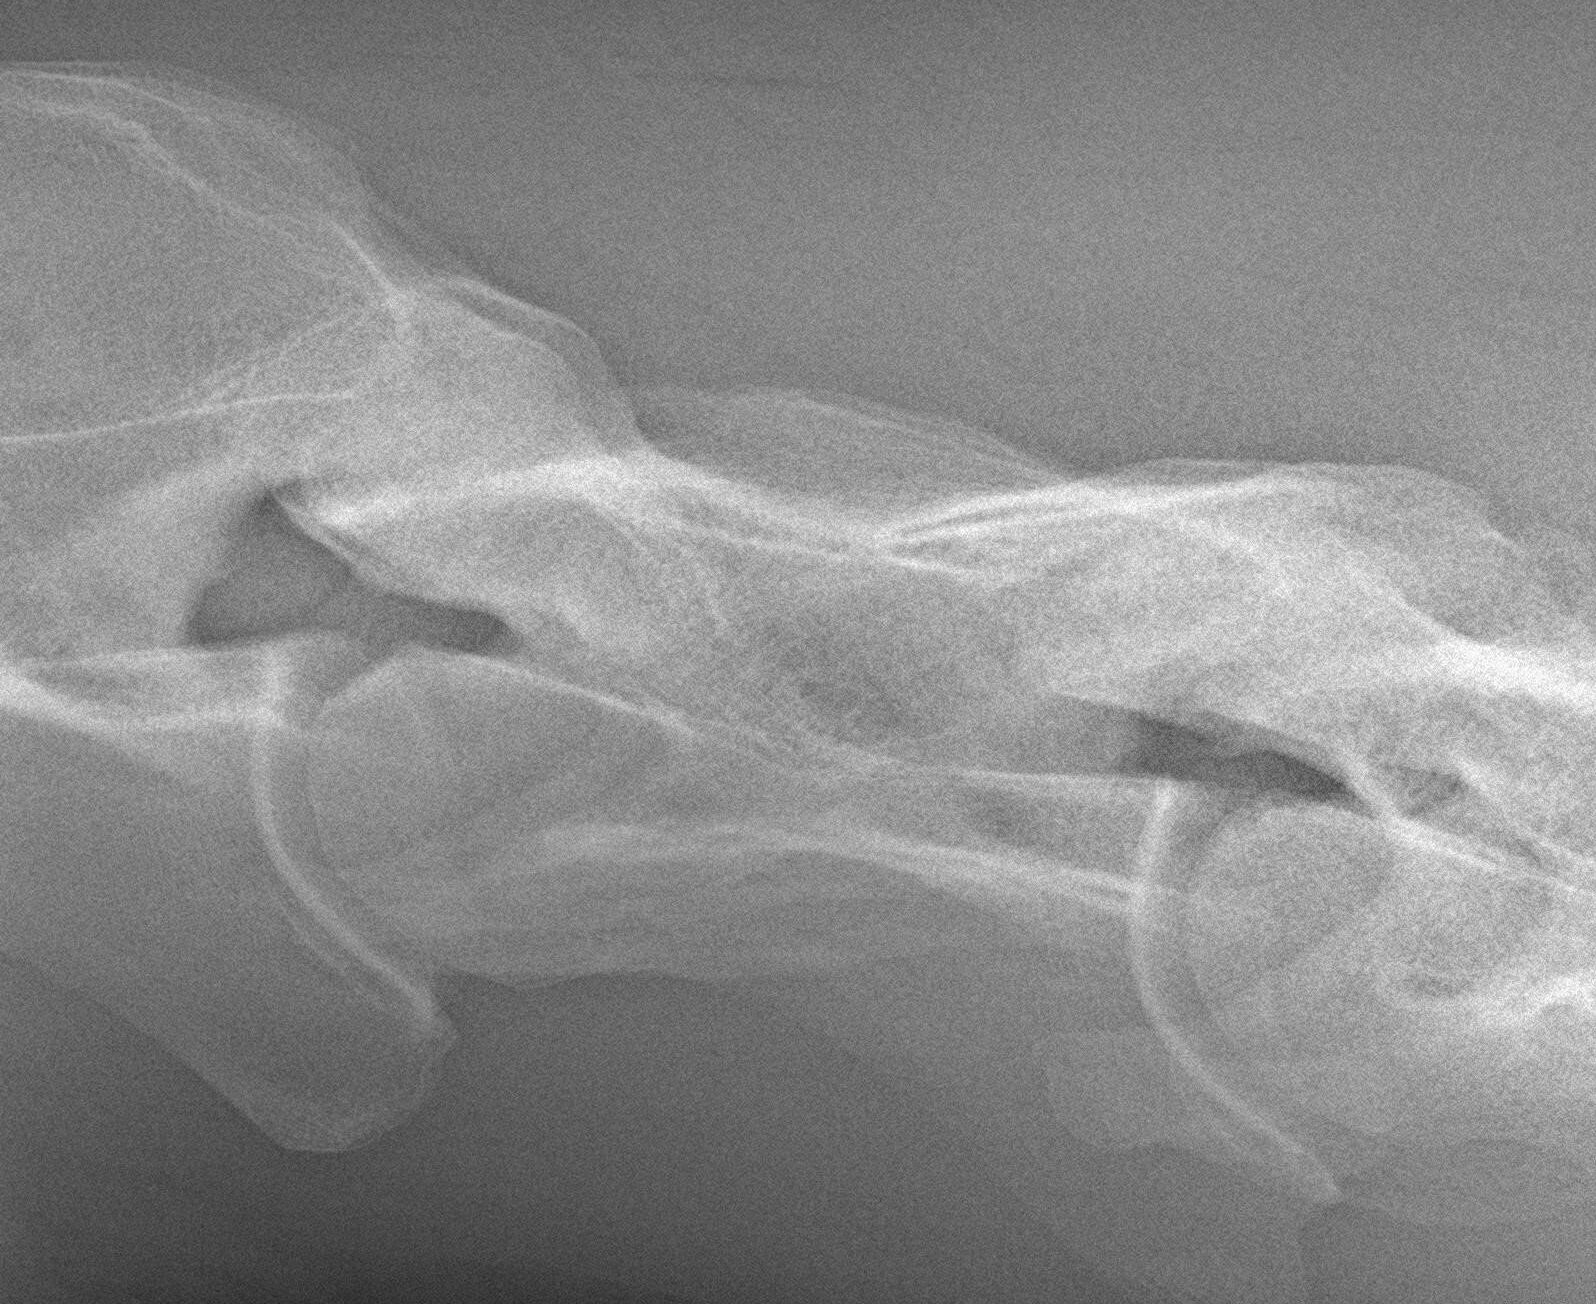

Once the pain site is localized, medical imaging is applied to arrive at a correct diagnosis and thus to initiate appropriate treatment.

Tendon problems?

The cause of lameness is very often related to soft tissue problems.

Thanks to the specialized trainings, we can apply the correct treatment by a correct diagnosis and the use of ultrasound.

Ultrasound examination is indispensable to clarify which tendon is injured and in which stage this injury is located.